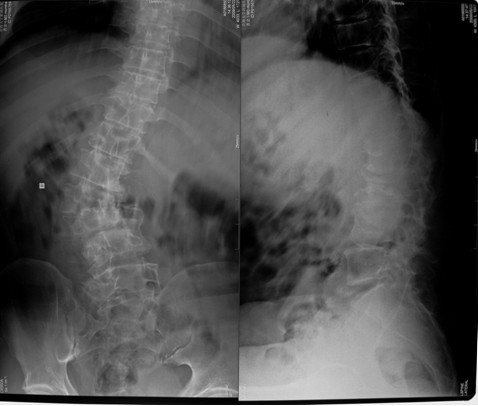

本组46例中男28 例,女18 例。年龄17~67岁,病程6 个月~7年,平均11.3 个月。本组患者均为 L1~S1腰段结核。病灶累及2 个椎体31例(L1-2 6例, L2-3 8例,L3-4 10例,L4-5 5例,L5-S1 2例),3 个或3 个以上椎体15例。合并腰大肌脓肿23列,所有患者均有腰背部疼痛,活动受限,双下肢感觉麻木19例,会阴部感觉减退12例,双下肢肌力减弱12例,腱反射减弱12例,术前后凸角(Cobb 角) <30°者12例, 30°~60°者28 例, >60°者6 例,Cobb角平均32.3°4例患者是二次手术。术前均行X线片、CT或者MRI检查。术后病理检查确诊为脊柱结核。

图11-a术前